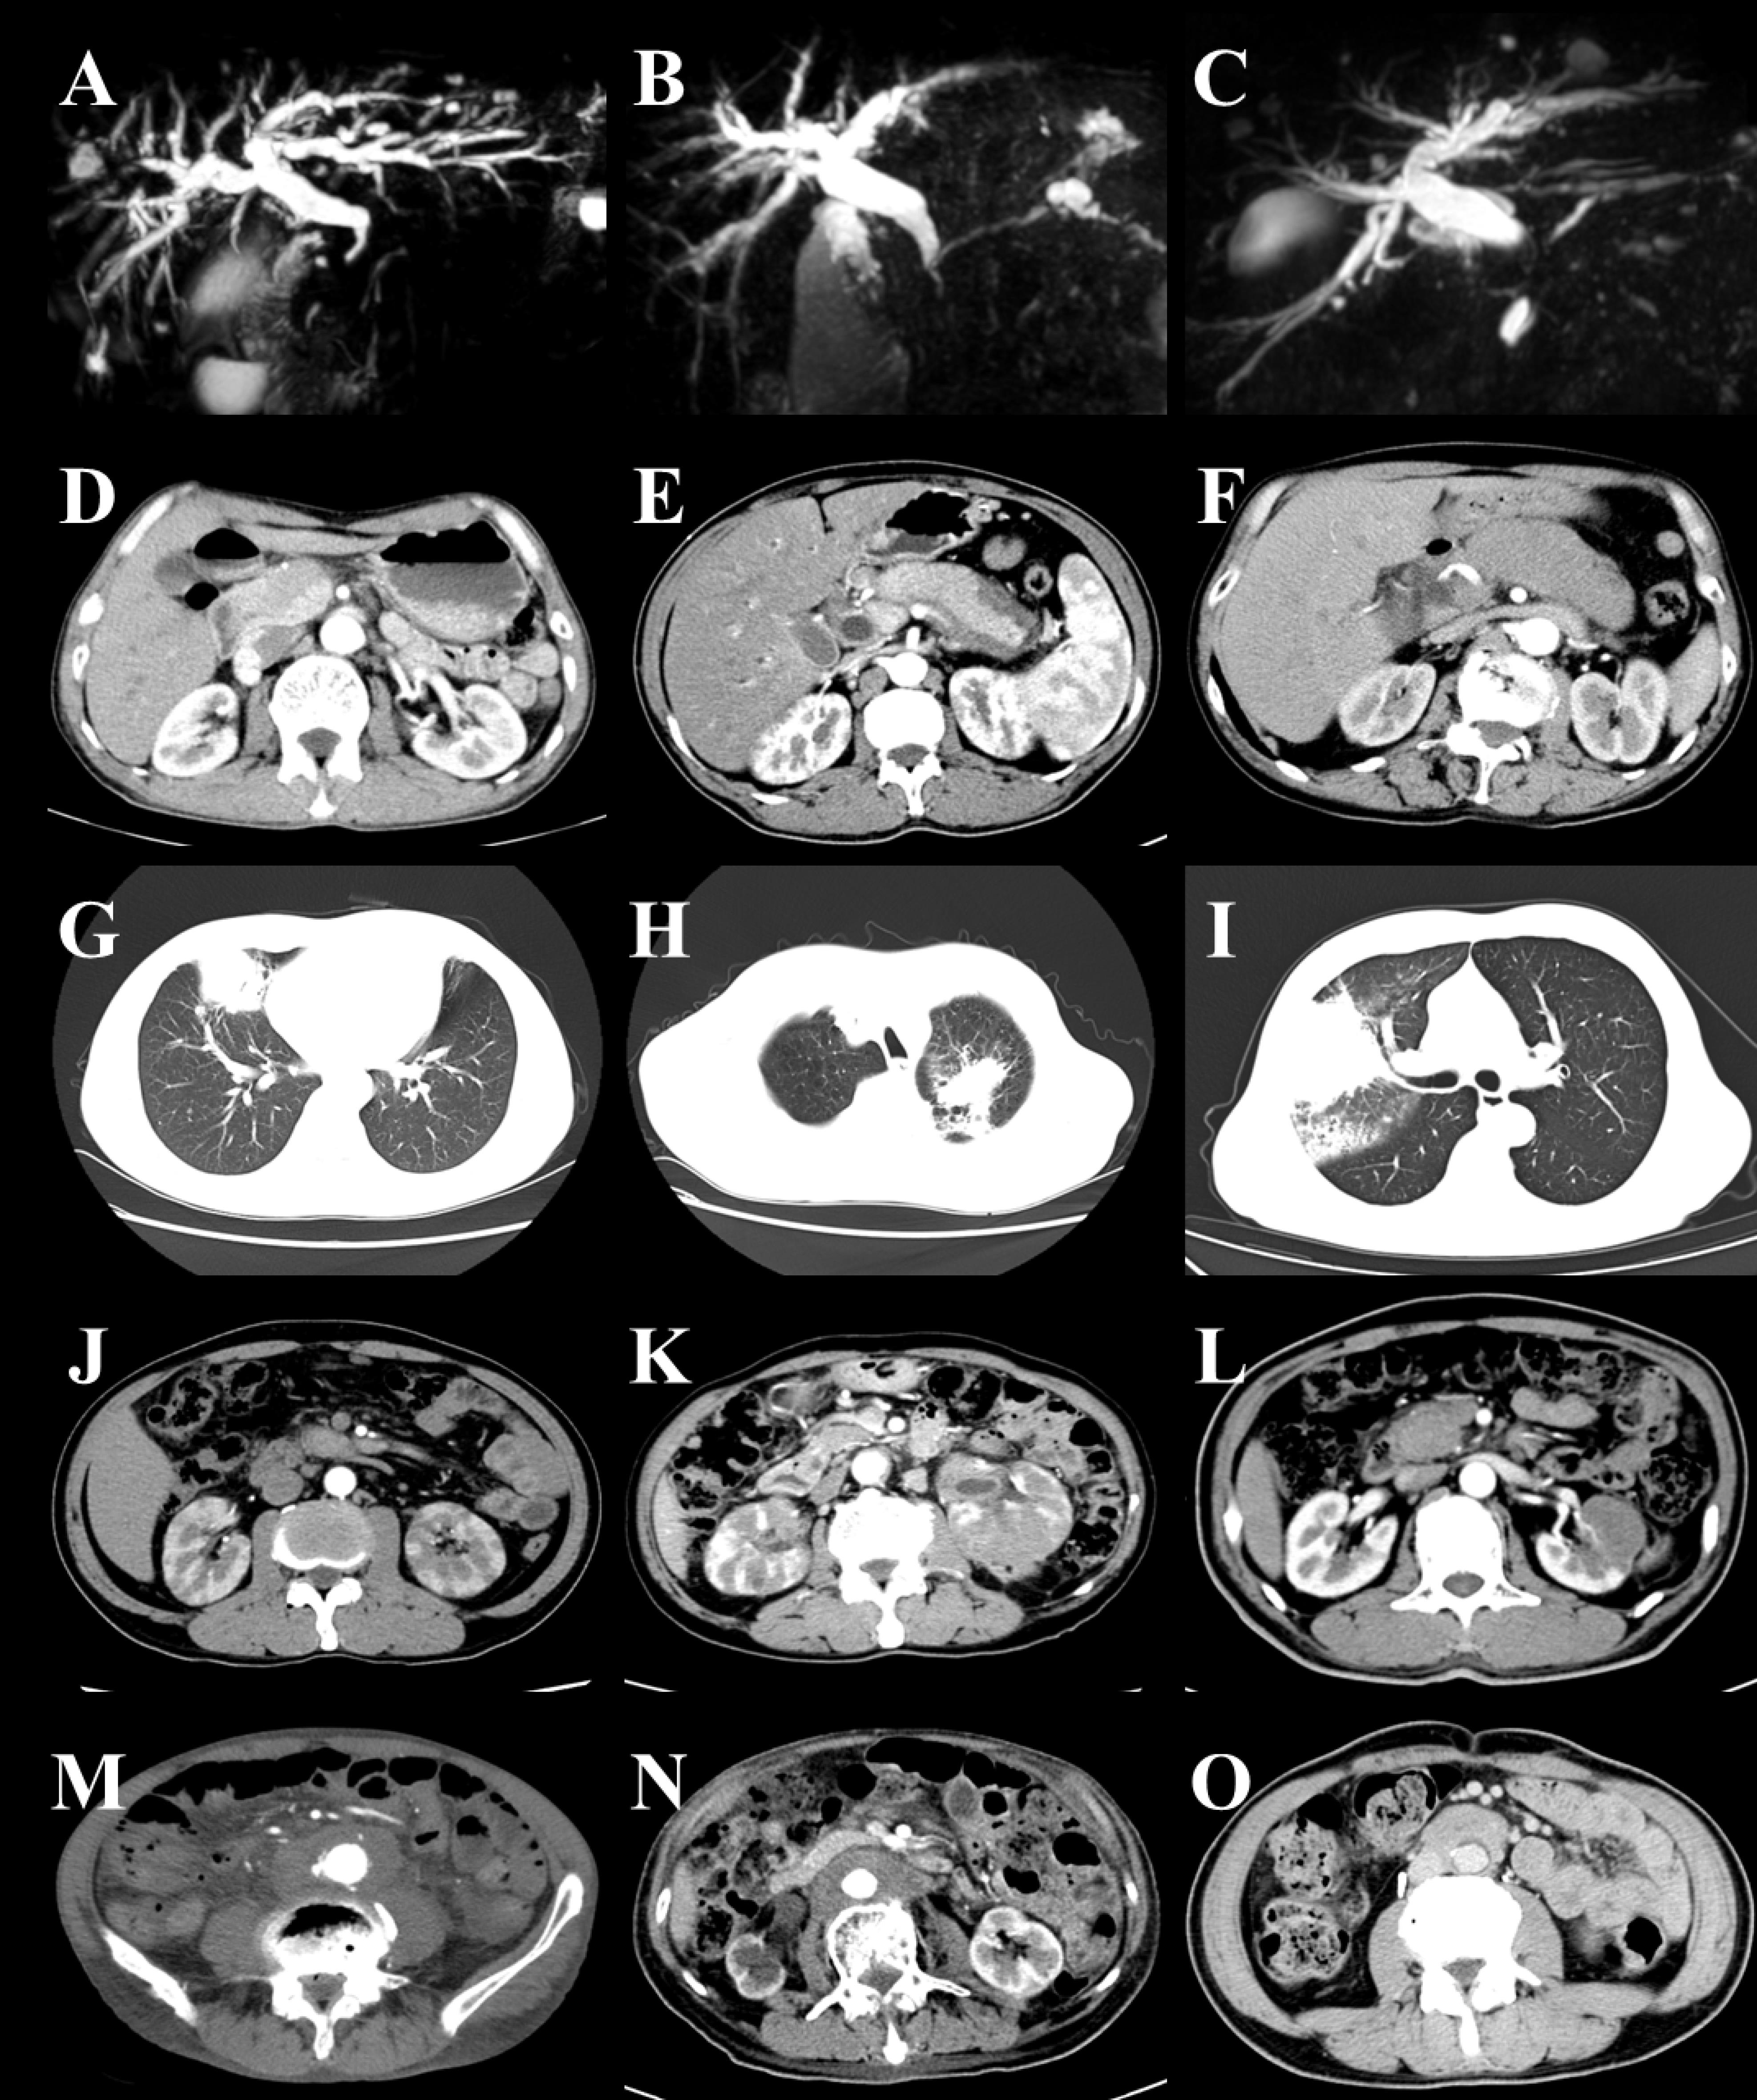

All 40 patients with IgG4-related autoimmune pancreatitis underwent imaging studies, including CT, MRI, or MRCP scans (Figure 2A-F). Twenty-three patients (57.50%) exhibited diffuse pancreatic enlargement, with the majority displaying a ‘sausage-like’ appearance. Seventeen patients (42.50%) exhibited focal pancreatic enlargement, with 15 patients (88.24%) affected in the pancreatic head, one patient (5.88%) with involvement of the uncinate process, and one patient (5.88%) with involvement of both the pancreatic head and the uncinate process. Additionally, 11 patients (27.50%) presented with pancreatic duct dilation, and one patient (2.50%) had a pancreatic pseudocyst. Furthermore, 20 patients (50.00%) with IgG4-related autoimmune pancreatitis were concurrently diagnosed with IgG4-related sclerosing cholangitis (IgG4-SC). Among these, 7 patients (35.00%) exhibited involvement of the distal common bile ducts, and 5 patients (25.00%) had both distal common bile ducts and proximal intrahepatic bile ducts involvement, accompanied by dilation of the proximal common bile ducts. Additionally, 6 patients (30.00%) showed involvement of the distal common bile ducts and extensive intrahepatic bile ducts, also with dilation of the proximal common bile ducts, while 2 patients (10.00%) had exclusive involvement of the hilar bile ducts.

Figure 2.

Features of Imaging in IgG4-RD. Bile duct: narrowing of the distal common bile duct (A–C). Pancreas: focal enlargement of pancreatic head (D), diffuse pancreatic enlargement (E–F). Lung: solid nodule (G), patchy infiltrate (H–I). Kidney: hypodense shadow (J–L).Retroperitoneal fibrosis: diffuse retroperitoneal involvement (M–N), encasement of the aorta (O)

Lung

All 17 patients with IgG4-related lung disease underwent CT scans (Figure 2G-I). Among these, 8 patients (47.06%) exhibited solid nodules, 5 patients (29.41%) presented with patchy infiltrates, one patient (5.88%) demonstrated interstitial changes in the alveoli, one patient (5.88%) showed both broncho-vascular and patchy infiltrates, one patient (5.88%) revealed a combination of patchy infiltrates and interstitial changes in the alveoli, and one patient (5.88%) exhibited both solid nodules and interstitial changes in the alveoli.

Kidneys and Retroperitoneal Fibrosis

Among 9 patients diagnosed with IgG4-related kidney disease, 5 patients underwent CT scans (Figure 2J-L). The imaging findings for all patients (100%) revealed hypodense shadows in the kidneys.

All 6 patients with IgG4-related retroperitoneal fibrosis underwent CT scans (Figure 2M-O). Imaging findings revealed that 2 patients (33.33%) presented with encasement of the aorta, while 4 patients (66.67%) demonstrated diffuse retroperitoneal involvement.